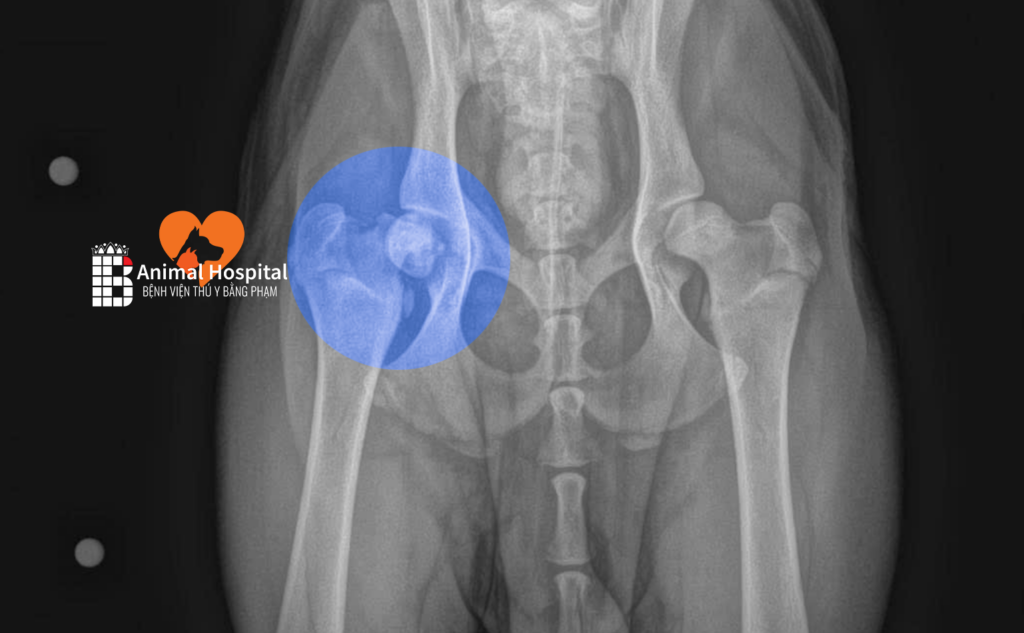

Tại đây, kết quả chụp X-quang cho thấy Nâu bị tổn thương cực kỳ nặng tại khớp háng. Về mặt giải phẫu, khớp háng có cấu trúc “khối cầu – ổ cối” kết nối xương chậu và xương đùi, đóng vai trò thiết yếu giúp khớp linh hoạt ở nhiều góc độ để thực hiện các hoạt động đi lại, chạy nhảy và giữ thăng bằng.

Cú ngã đập mạnh xuống nền đường cứng đã tác động trực tiếp vào vùng mấu chuyển lớn của bé. Hậu quả là Nâu bị gãy ở cổ xương đùi, tức là vị trí nằm ngay giữa chỏm và khối mấu chuyển của xương đùi. Đây là một dạng chấn thương rất phức tạp.